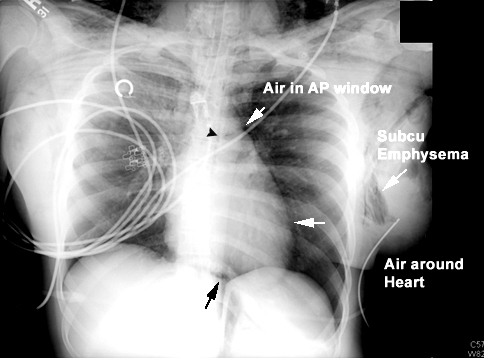

32 year old female with a history of asthma. Presented with severe shortness of breath and wheezing after running out of her inhalers. She was intubated in the ED and brought to the MICU.